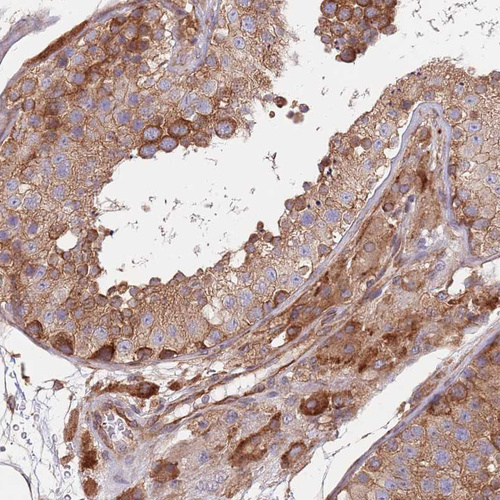

Immunohistochemical staining of human testis shows strong granular cytoplasmic positivity in cells in seminiferous ducts and leydig cells.